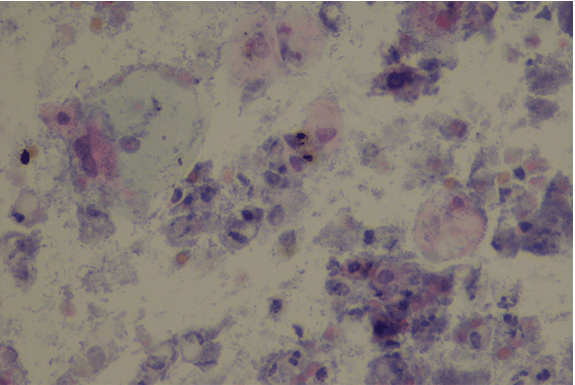

The first result obtained was bladder cytology that showed reactive transitional cells, with lots of histiocytes, containing a brown-blackish pigment, positive for Masson-Fontana technique (Figure 3).

Figure 3: Reactive transitional cells with lots of histiocytes containing a brown-blackish pigment (Masson-Fontana positive).